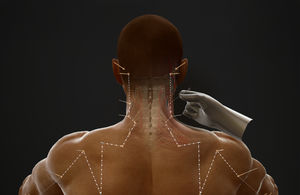

... también simular técnicas de acupuntura en varios acupuntos con retroalimentación háptica instantánea y herramientas de visualización interactivas que incluyen información de profundidad y lecturas de inserción de ángulos. 14 meridianos ...